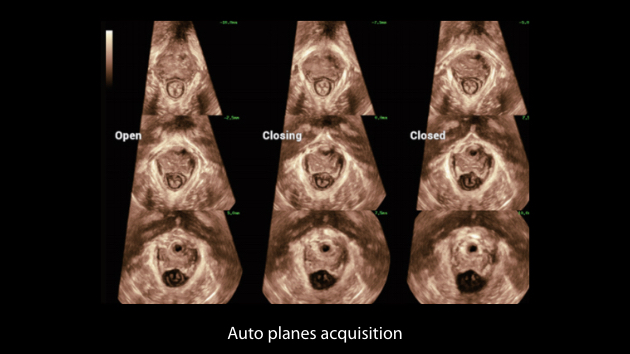

Nuewa I9? ??? ???? ?? ??? ?? ??? ???? ?? ??? ???? ???? ??? ?????. ??? ??? ??? ?? ????? ?? ???? ???? ???? ???? ??? ???? ??? ??? ???? ??? ???? ??? ?? ?????.

ZST+ ???? ???? ??? ???? ??? ?????. ??? ????? ??? ? ???? ?? ??? ?? ????? ?????. ?? ???, ?? ???, ?? ??? ?? ?? ?? ??? ??? ???? ???? ??? ?? ??? ?? ???? ?? ??? ?? ??? ?????.